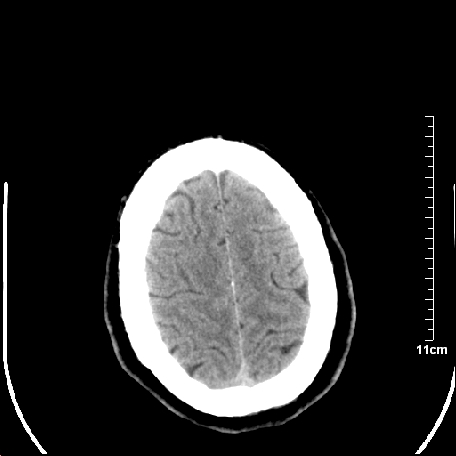

双侧外侧裂,左侧脑沟见高密度结节影,边清,还有鞍上池层面密度也高

靠,老年脑,没什么病。

都是血管。

脑血管硬化?高血红蛋白症?

高血红蛋白症可能

高血红蛋白症

高血红蛋白血征

基底动脉硬化迂曲。高血红蛋白血症。